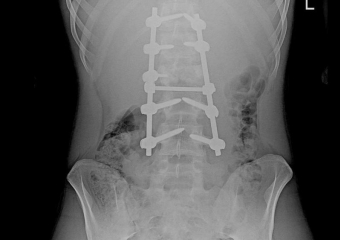

Воронежские врачи вернули 16-летнему подростку возможность ходить после тяжёлой травмы

Парень прошёл трудный путь после получения переломов и операций. Воронежские врачи вернули 16-летнему подростку возможность ходить после тяжёло...